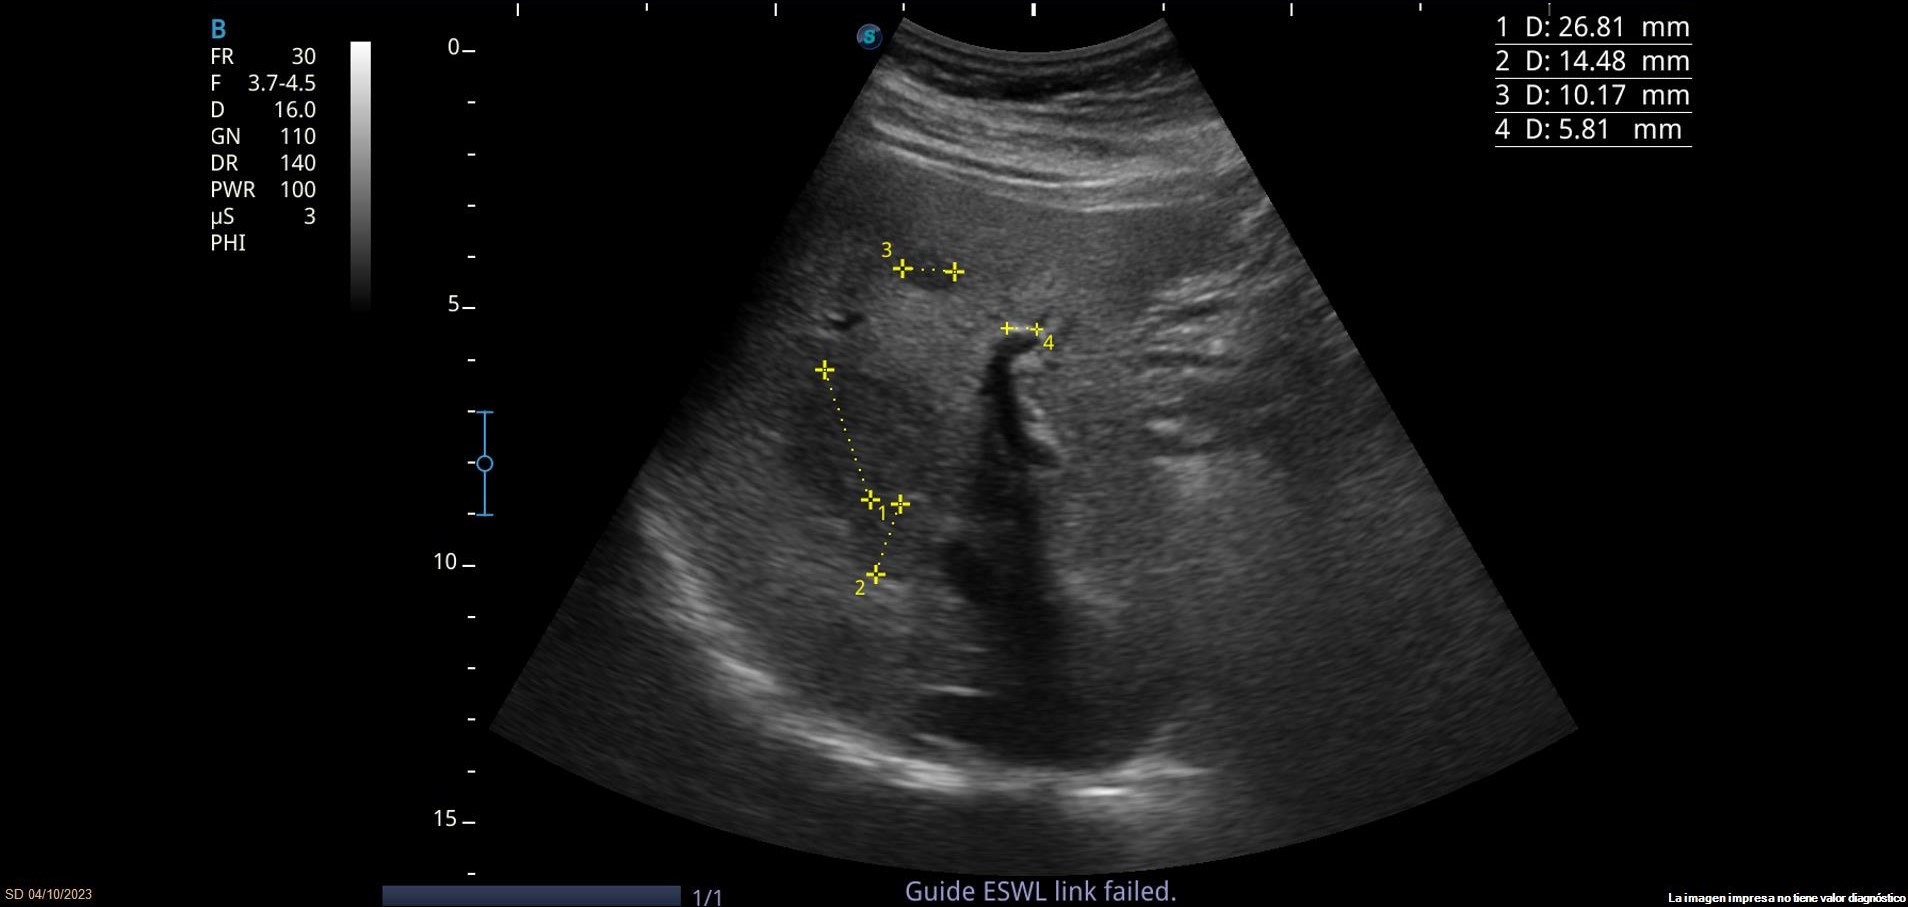

Se observan varias LOEs (lesiones ocupantes de espacio) hepáticas isoecoicas con parénquima hepático, la mayor de 3.5cm de diámetro, con leve vascularización. También se observa lesión hiperecoica con sombra posterior en parénquima hepático, sugerente de litiasis.